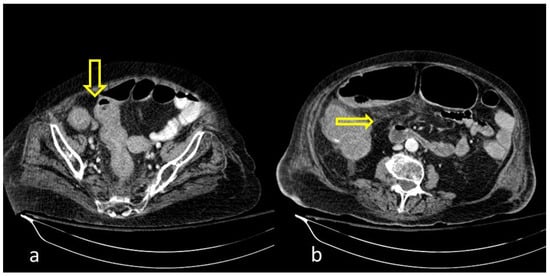

Figure 11. A 75-year-old intubated patient with COVID-19 presented with hematemesis, hypotension and acute drop of hemoglobin level. Computed Tomography revealed active intraluminal extravasation of contrast into the 2nd part of duodenum (arrow) on arterial phase (a). Further pooling of the contrast (arrowhead) is shown on portal phase (b).

GI hemorrhage is less commonly encountered in abdominal imaging, and CT findings include active intraluminal extravasation of contrast and indirect signs such as luminal distention with blood clots (Figure 11) [56].

Imaging is additionally significant to the treatment plan by identifying the exact site and extent of the bleeding as well as offering a precise and minimally invasive treatment option. Digital Subtraction Angiography can confirm the active bleeding seen as a “contrast blush”, detect the responsible branch and provide occlusion via selective embolization.